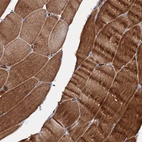

Immunohistochemical staining of human Skeletal muscle shows strong cytoplasmic positivity in myocytes.